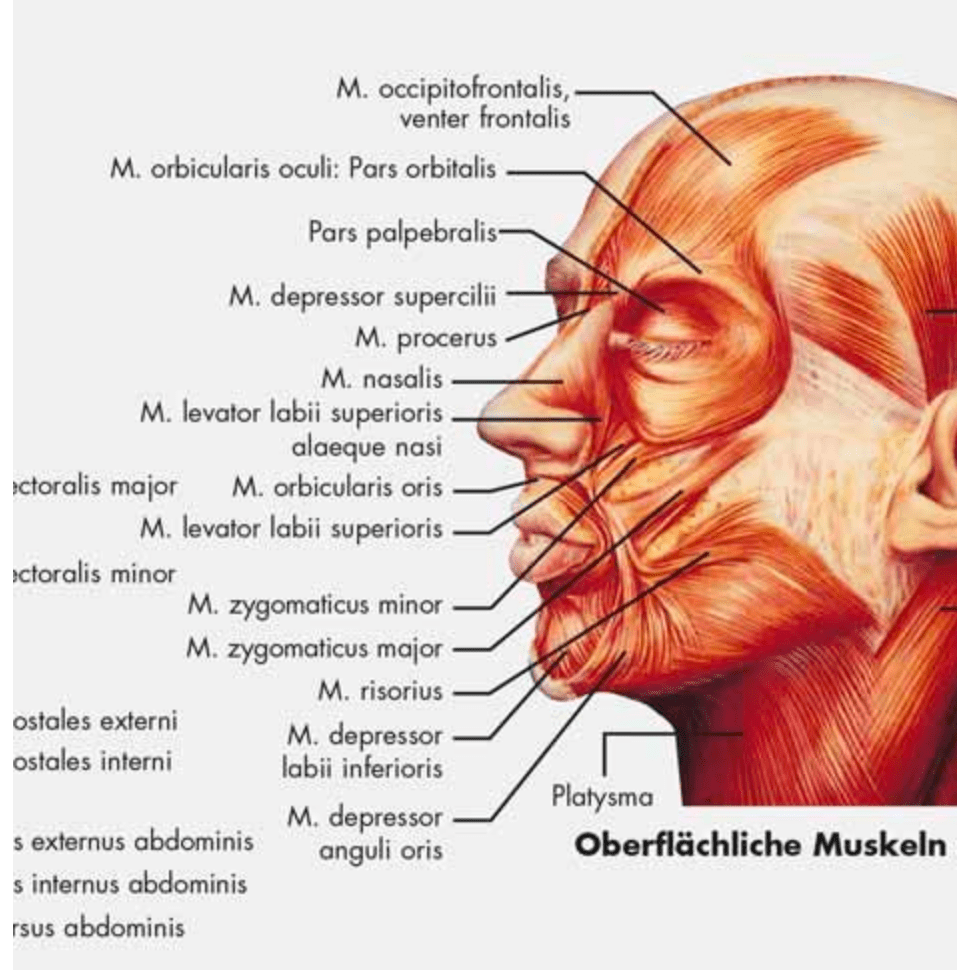

Muscle posters

Muscles provide movement to the musculoskeletal system, and their origins, insertions and lodges are clinically important for every healthcare professional. That is why we at eAnatomi have both developed and designed our own anatomy posters, which provide the ultimate overview of all the muscles of the body. On this page you can find both our own posters and posters from other manufacturers. We offer posters in several different languages such as pure Latin, Danish, English and Swedish, etc.